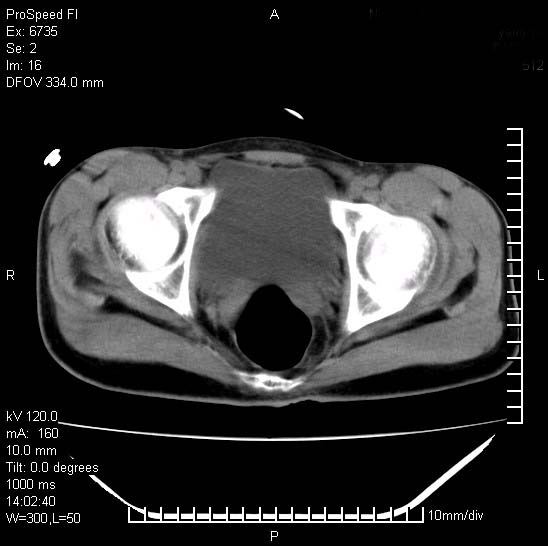

患者自诉胯部疼痛两年余,在当地服用中药,半月前至本院考虑骶髂关节结核,给予抗痨治疗。现发展至右下肢疼痛明显,活动受限,以膝关节处明显,拍膝关节平片无明显异常。

两侧骶骼关节改变,考虑强直性脊炎

左侧骶髂关节面限局性骨破坏,边缘硬化关节腔见钙化物;不出外tb

右侧骶髂关节也有类似改变,只是较左侧轻,首先考虑强直性脊柱炎,不除外结核,建议作hla-b27检查。

典型强脊炎改变,髋关节亦有累及

符合强直性脊柱炎表现。